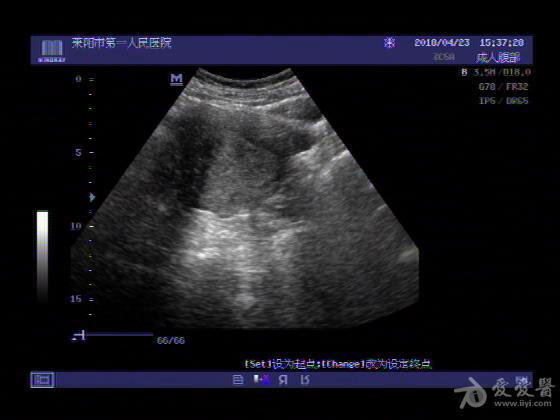

女,48岁,月经量多,两个月,一年前出现过类似现象,刮宫吃药后缓解。

超声可见:子宫内膜显著增厚,后肌壁内膜可见范围约3.27X0.90CM低回声区,CDFI显示较丰富线样血流,宫底宫腔内见类**状低回声结节。前肌壁见多发类圆形低回声结节。

超声提示:子宫内膜增厚(建议刮宫病理),子宫多发肌瘤

病理结果:内膜增生